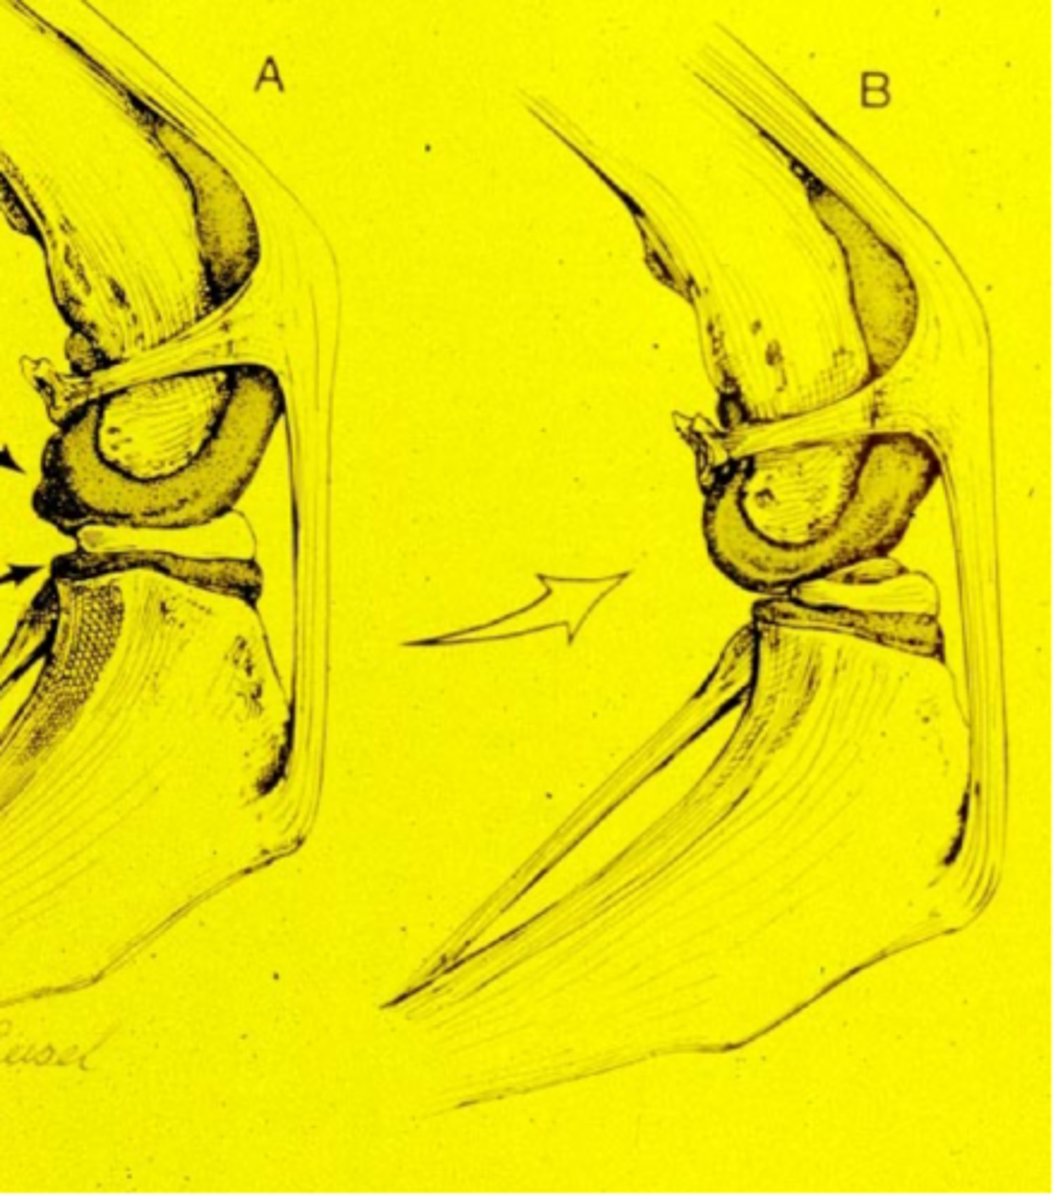

transverse radial tear

A

longitudinal or bucket handle tear

B

medial peripheral detachment w/ shredding of cartilage

C

folded caudal horn

D